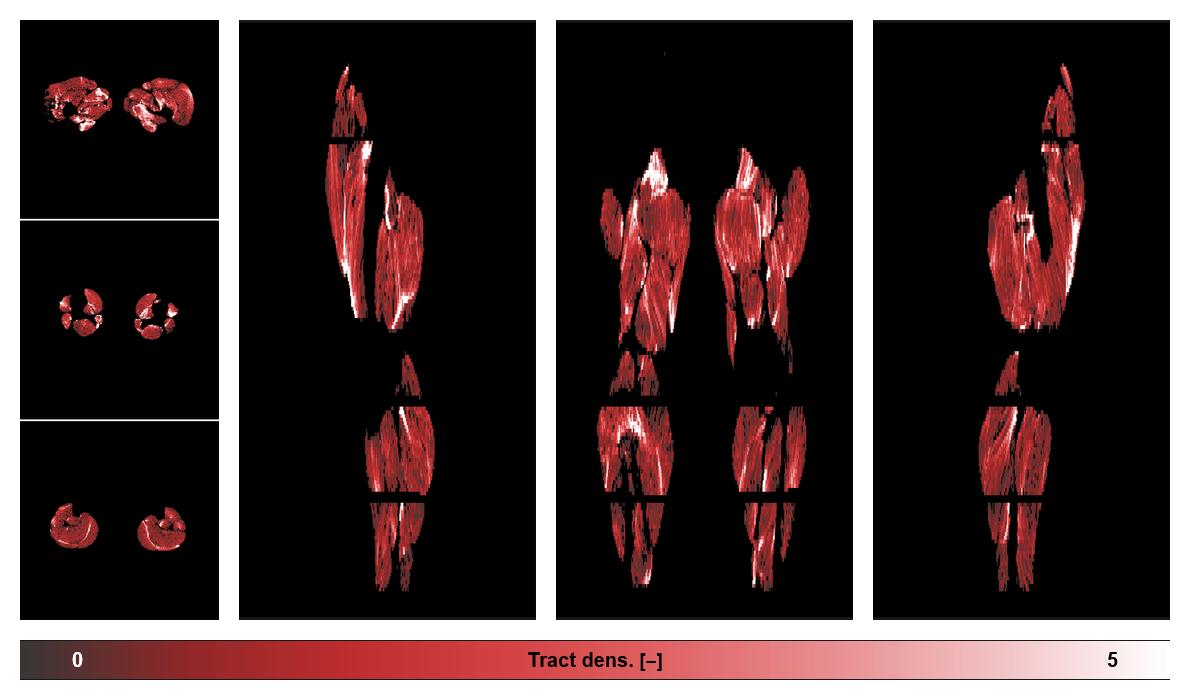

• Muscle fiber density map

Muscle fiber tract density map based on whole leg DTI based fiber tractography.